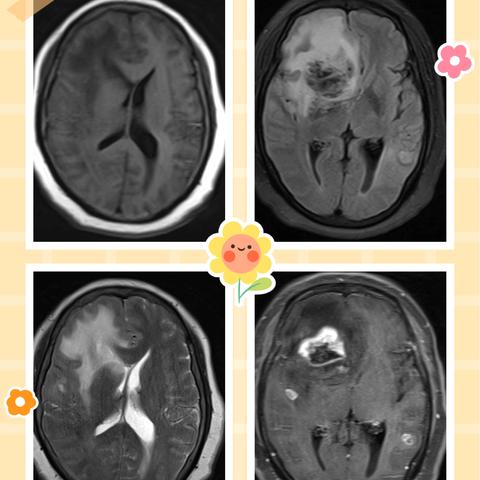

误为海绵状血管瘤的一种罕见疾病-心脏粘液瘤脑转移